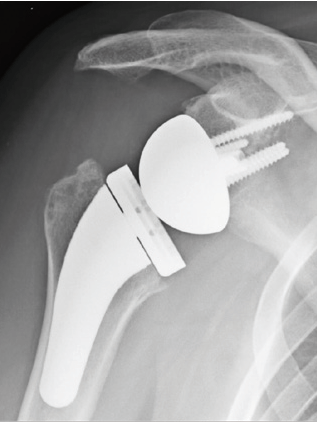

Dadurch wird der Drehpunkt des Schultergelenkes verlagert und ein anderer Hebelarm erreicht, dass der kräftige Schulterkappenmuskel (M. deltoideus) die Funktion der häufig nicht mehr vorhandenen Rotatorenmanschette übernehmen und ersetzten kann. Die inverse Schulterendoprothese bietet daher häufig in "verzweifelten Situationen" eine ausgezeichnete Behandlungsmöglichkeit. Im Fallbeispiel zeigt das Röntgenbild vor der Prothesenversorgung einen Zustand nach mehrfachen Operationen mit nach oben gerutschtem Oberarmkopf, Arthrose und Metallankern in der Pfanne. Die eingebaute inverse Prothese hat den Arm wieder nach unten gebracht, sodaß die Patientin den Arm nun wieder schmerzfrei nach oben heben kann ohne am Schulterdach zu reiben.